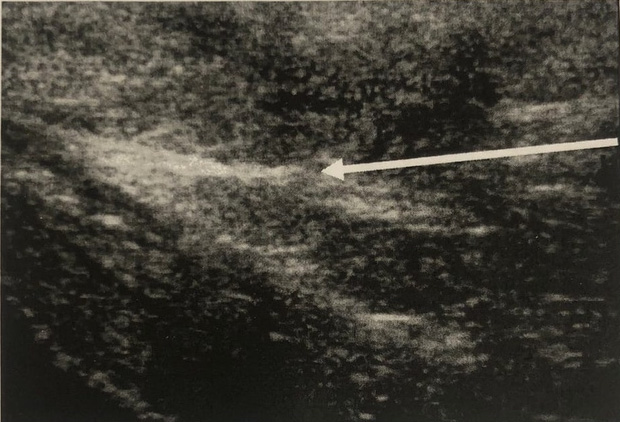

Продолжительность лазерного воздействия составляла 5,5–8,0 мин и контролировалось по УЗ-картине в реальном времени. Контроль процедуры лазерной облитерации осуществлялся в реальном времени и оценивался по образованию ультразвуковой гиперэхогенной зоны («облака»), возникающей в тканях на конце световода (рис. 2).

Рис. 2. Сонография копчиковой кисты во время лазерной облитерации: а – стрелка указывает на появление гиперэхогенного «облачка» во время лечения